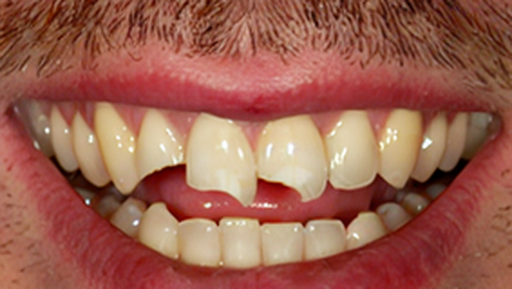

![]() |

| Fix damaged front teeth. | 0.9/0.8/0.9 | 0.0/0.5/0.8 | 0.7/0.6/0.5 | 0.0/0.0/0.7 | 0.2/0.5/0.6 | 0.9/0.9/0.7 | 0.0/0.4/0.9 | |

Each row includes the previous and ground truth images, followed by outputs from seven models. Scores below each output denote EA (Editing Accuracy), VQ (Visual Quality), and CP (Masked SSIM) (all in [0, 1] range).